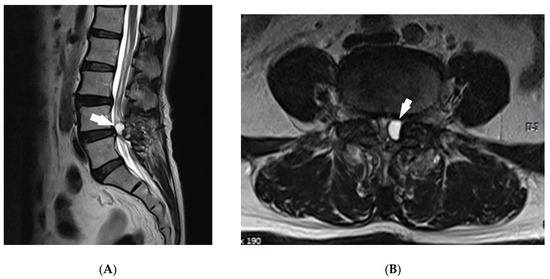

2. Case Report